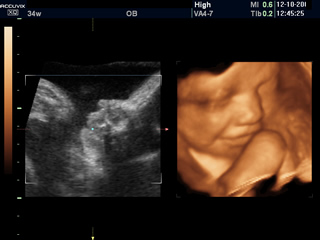

検診時は、毎回、超音波検査を行います。

※お腹の赤ちゃんのお顔を3Dのリアルタイム動画で見られる4D超音波検査は、12~13週以降に適宜行います。